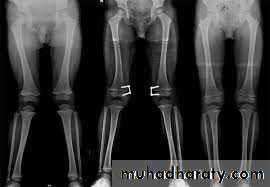

Bow legs & knock knee

in babies are so common that are consider to be normal stage of development (physiological) ; in addition to this , rickets may play a role in developing these deformities physiological or renal rickets .

Bilateral bow leg

Surgical correction is indicated after this age by stapling or osteotomy usually after the age of 10 .

BLOUNT’S DISEASE

It is progressive bow leg deformity due to abnormal growth of the posteromedial part of the proximal tibia epiphysis , which is some time fragmented ;the metaphysis is some what beak shape .

The deformity is usually bilateral and it is progressive .

The treatment is by corrective osteotomy .